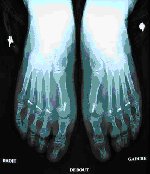

Traitement de métatarsalgies et des griffes d’orteils

Le traitement est la plupart du temps réalisé en association avec celui de l’hallux valgus.

Le traitement consiste en une ostéotomie des autres métatarsiens (ostéotomie de Weil). Ce geste fait reculer la tête métatarsienne ce qui a pour effet de décomprimer l’articulation. Les ostéotomies de Weil sont généralement fixées par une vis.

La première consultation post-opératoire a lieu dans le mois qui suit l’intervention pour réaliser un bilan radiologique et juger de la nécessité ou non d’une rééducation. Les consultations suivantes seront planifiées avec votre chirurgien selon vos progrès.